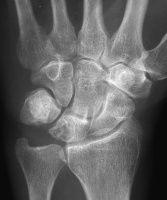

Clinical Example: Lunate Cyst

This imaging series was obtained for evaluation of a one month history of painful pronosupination in an active 85 year old man whose daily exercises include pushups.

lunate cyst